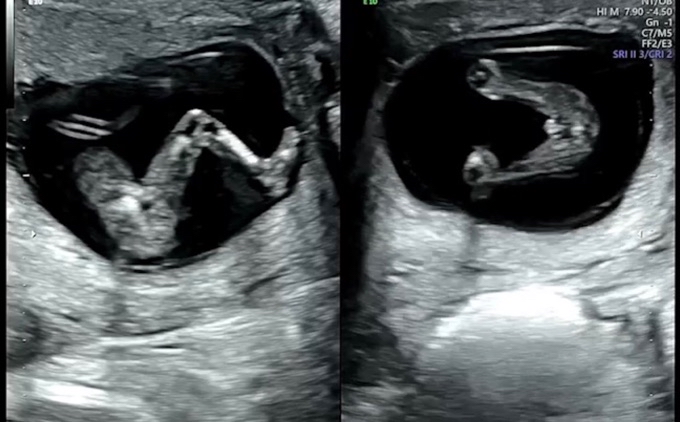

12주 초음파인데요 딸일까요 아들일까요?

아직 12주라 확실하진 않다고 하는데요

내심 딸을 바래서 이리보고 저리 보고 있어요

고수님들 알려주세요~